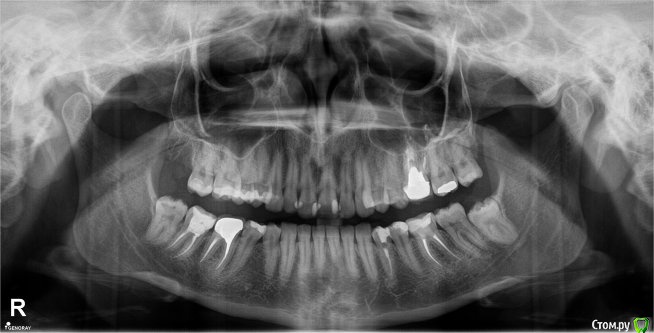

Добрый день. Год назад установила металлокерамическую коронку, ПОД ней вкладка хром-кобальт, каналы пролечены гуттаперчей запечатаны. Зуб до этого 10 лет находился под металокерам. коронкой установленной некачественно и каналы были пролечены резорц. пастой, зуб был красно-черный, коронка зуба была сформирована пломбой.

Так вот прошел год после того как переделали зуб, а у меня десневые сосочки с обеих стороны воспалены все это время, кровоточат при чистке щеткой, а особенно ирригатором, еда забивается так, что достать ее трудно даже ирригатором.

Вопрос, что можно сделать, можно ли переустановить коронку на циркониевую не меняя вкладку. Так как врач который переделывал говорил, что достать будет уже не возможно только удалять. Рядом стоящий зуб очень с большой пломбой, нужно ли его перелечивать? (7 ка). Коронка стоит на 6-ке нижней. Успокоится ли десна после переустановки коронки. Заранее благодарна за ответы.